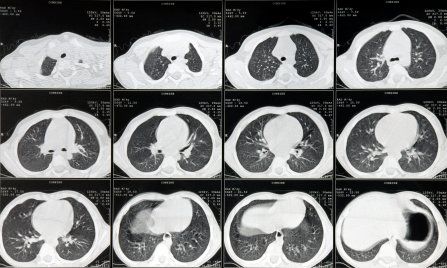

A retrospective analysis suggested that a declining proportion of patients with lung cancer would meet the criteria for undergoing low-dose computed tomography (LDCT) screening. This is largely due to changes in smoking habits, and highlights the possibility that revised criteria may be necessary.

Based on results from the National Lung Screening Trial, the USPSTF guidelines recommend annual screening with LDCT for adults aged 55 to 80 years who have a 30 pack-year history of smoking and who currently smoke or have quit within the last 15 years. The guidelines specifically recommend discontinuing screening once a person has not smoked for 15 years.

“We observed a decline in the relative proportion of patients with lung cancer meeting the USPSTF criteria,” the authors wrote. That proportion dropped from 56.8% in the 1984-1990 period down to 43.3% in the 2005-2011 period. The decrease was significant in both men and women.